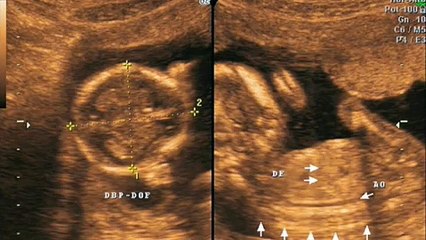

El precio del perdón: Elena presenta ecografías de un embarazo falso para amarrar a su ex